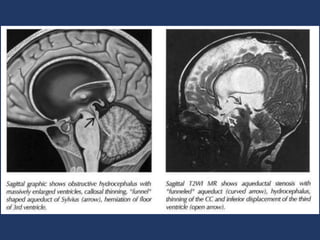

Aqueductal stenosis • Bestdiagnostic clue • Funnel-shaped aqueduct of Sylvius • "Ballooned" ventricles (lateral, third) and foramina of Monroe proximal to obstruction • Normal fourth ventricle and foramina (Luschka, Magendie) distal to obstruction • Interstitial edema with indistinct ("blurred") ventricular margins (absent if AS "arrested") • Location: • Stenosis at cerebral aqueduct, either at level of the superior colliculi or at intercollicular sulcus • Size: • Normal mean cross-sectional area of the aqueduct at birth is 0.2 to 1.8 mm2 • Morphology • Typically funnel-shaped aqueduct of Sylvius • May see "aqueductal forking" or branching of aqueduct into channels • Aqueductal forking often accompanied by fusion of quadrigeminal bodies, third nerve nuclei or tectal beaking

MR Findings • TlWI oLateral ventricles enlarged o Corpus callosum (CC) thinned, stretched upward o Fornix, internal cerebral veins, 3rd ventricle floor displaced downward • T2WI o "Fingers" of CSF-like hyperintensity extend outwards from ventricles into brain (including CC) o Interstitial edema most striking around ventricular horns o Disturbed/turbulent CSF flow in ventricles o Absent aqueductal "flow void" common